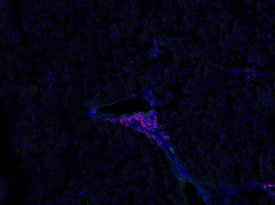

Eosinophil infiltration into the liver during a H. polygyrus infection. This image shows a branch of the hepatic portal vein in an infected mouse. Red marks infiltrating Eosinophils; green is endothelial cells.

Rufus uses mice to study the hepatic response to H. polygyrus infection and has begun to unravel how the immune system coordinates its response to gastrointestinal disruptions. His research so far has shown that there are two temporally distinct immune responses to infection likely related to the nematode’s life cycle. The nature of these sequential immune responses is also distinct: the initial response at day 3 is marked by a profound increase in a particular type of monocyte (white blood cell) and activation of other myeloid cells including macrophages. In contrast, the response at day 7 involved a Th2 response in the form of eosinophilia, comparable to the response previously observed in the peritoneal cavity.